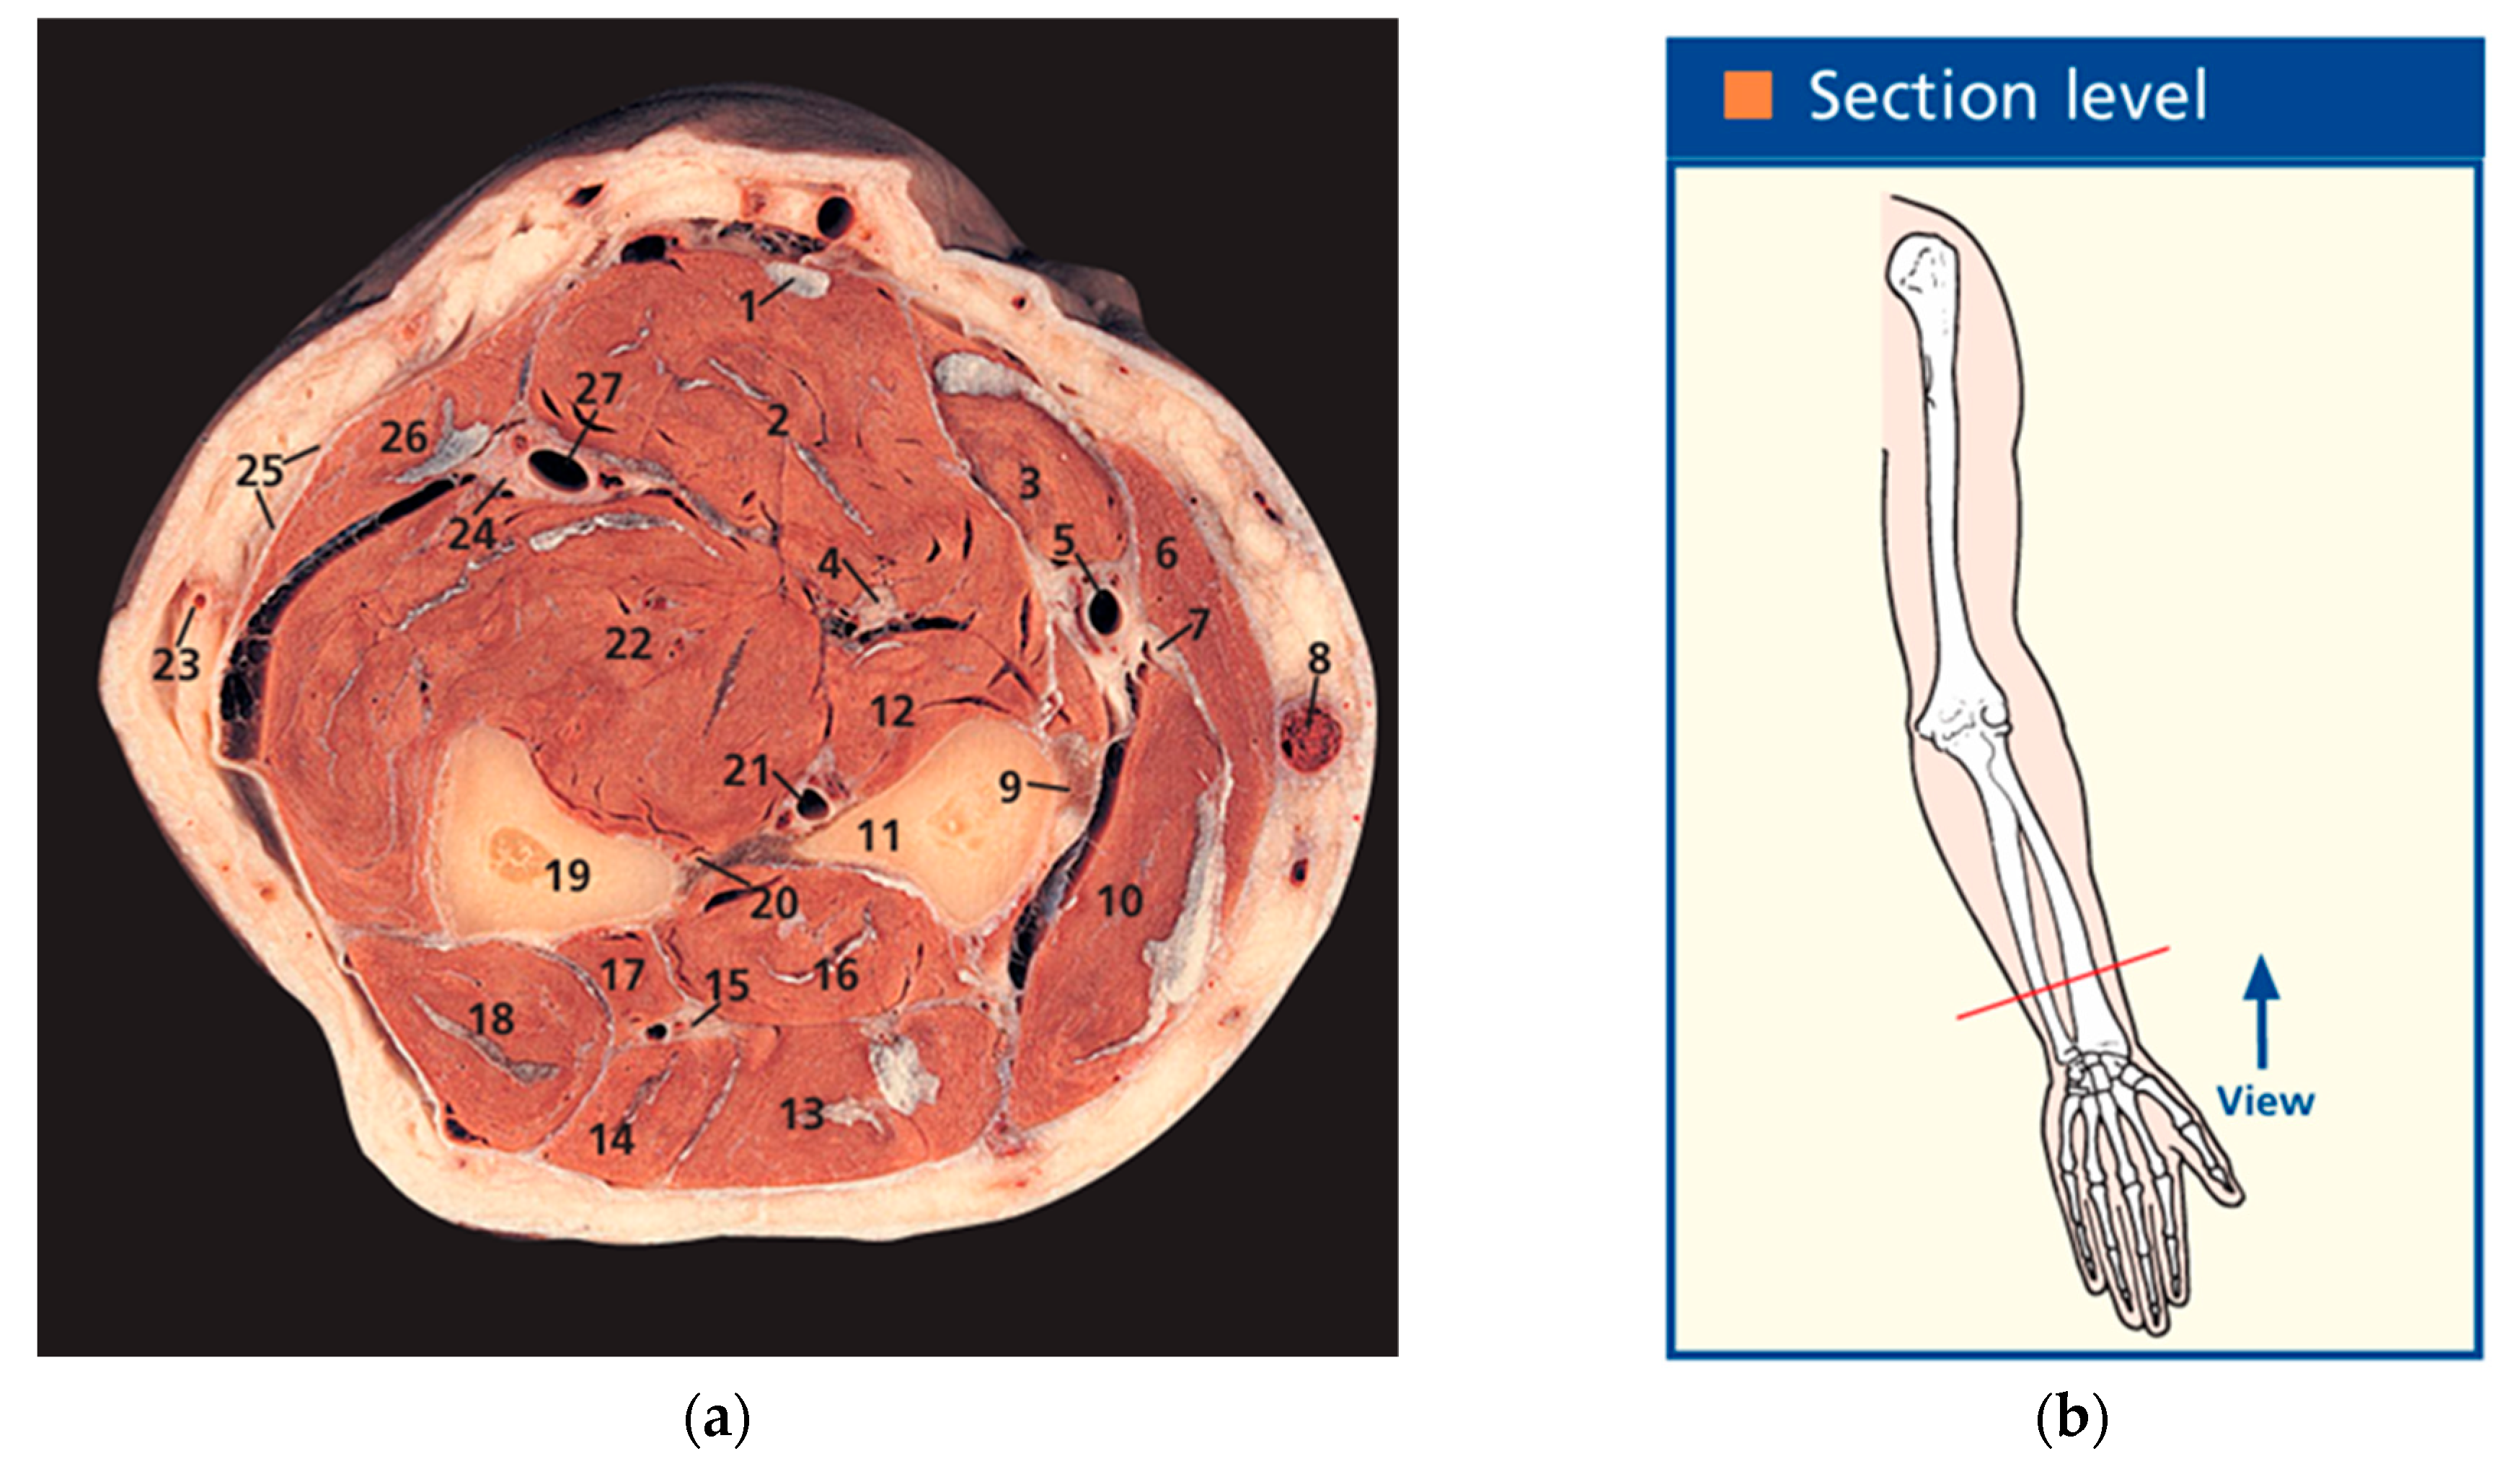

3.1. Construction of the Forearm Muscles’ Volumetric Models

- Ellis, H.; Logan, B.M.; Dixon, A.K. Human Sectional Anatomy: Atlas of Body Sections, CT and MRI Images, 3rd ed.; Hodder Arnold: London, UK, 2010; Volume 92, pp. 178–179. [Google Scholar] [CrossRef]